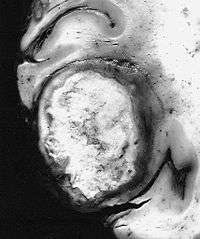

Some glioblastomas, such as this giant-cell variant, are discrete firm masses which clinically and radiographically simulate metastatic carcinoma